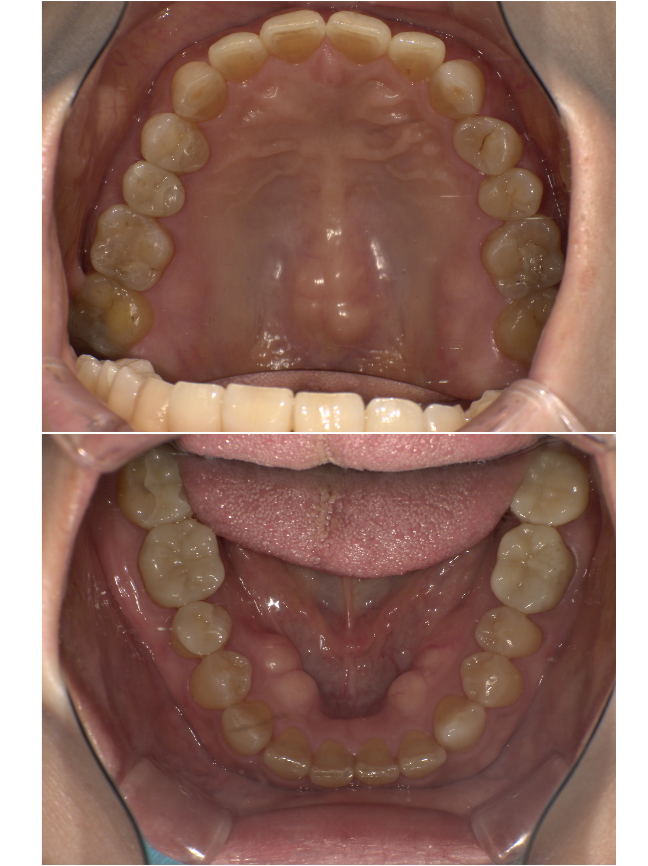

| 治療内容 | 全顎治療 |

|---|---|

| 主訴 | 左上の歯が噛んだら痛い。全体をしっかり治したい |

| 診断 | 左上7根尖性歯周炎、全体的にかぶせ物が合っておらず、むし歯のリスクが高い状況でした |

| 治療期間 | 11か月 |

| 治療費用 | 補綴費用¥1,840,000-+ホワイトニング |

| リスクと副作用 |

|

| 院長コメント | とてもお優しい60代女性の方です。聞こえに困難のある方だったので、筆談を毎回行いました。どうしても時間はかかってしまいますが、当院のコンセプトの「しっかりとお伝えする」を行い、カウンセリングと説明を丁寧に2時間ほど行いました。受け口に関しては外科矯正が必要だったので希望されませんでした。かぶせ物に隙間ができていた事、金属のかぶせ物は厳密には歯と接着していないことをお伝えしたところ、長持ちする歯を希望されたのでジルコニア修復治療およびダイレクトボンディングを行いました。一本ずつ治療する際もマイクロレベルでかみ合わせの調整を行い、ずれないよう注意しました。ホワイトニングもする予定だったのであらかじめかぶせ物を予定される白さに設定しました。治療終了後、結果にとても満足され、今でもメインテナンスで通っていただき、笑顔でお話してくださいます。 |